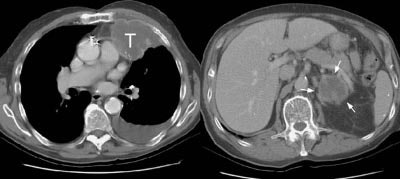

Example 1: This patient with non-small-cell lung cancer had a large necrotic primary tumor (T) and a large left adrenal metastasis (white arrows).

NOTE: Click image to enlarge